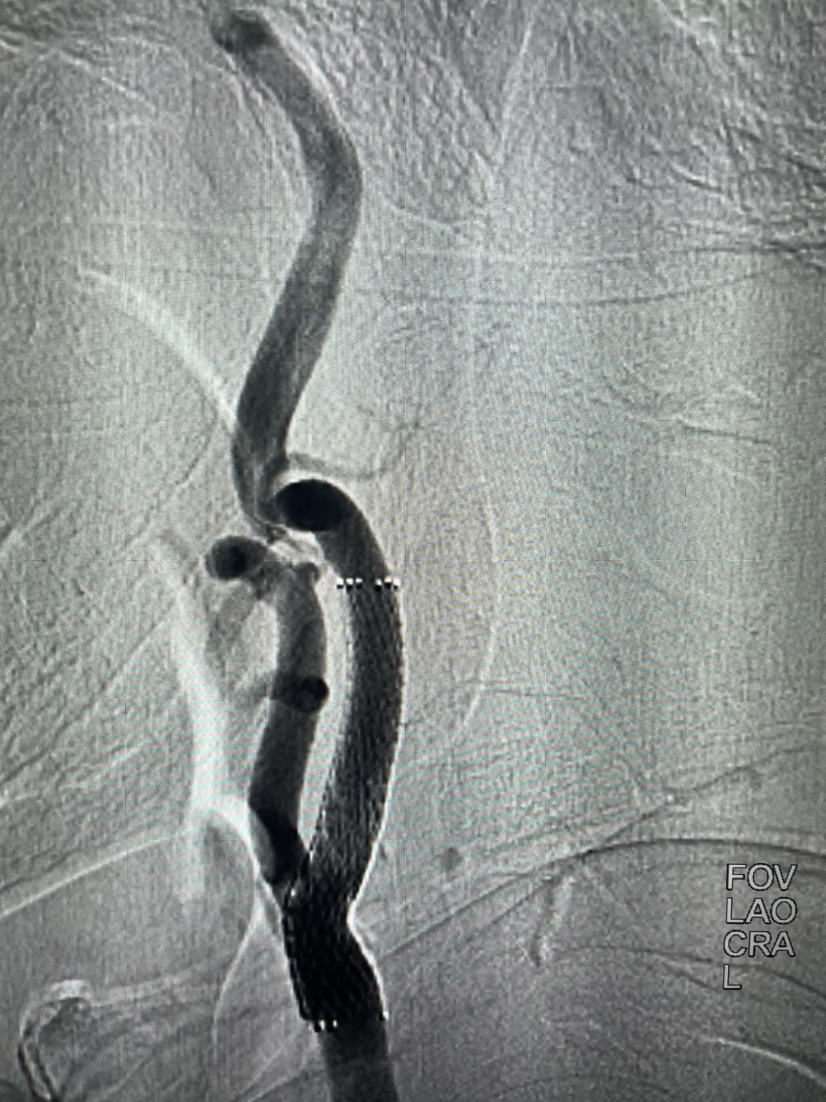

支架植入后正位

支架植入后侧位